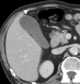

Normal gallbladder folds

In vertebrates, the gallbladder is a small hollow organ where bile is stored and concentrated before it is released into the small intestine. In humans, the pear-shaped gallbladder lies beneath the liver, although the structure and position of the gallbladder can vary significantly among animal species. [Source: Wikipedia ]